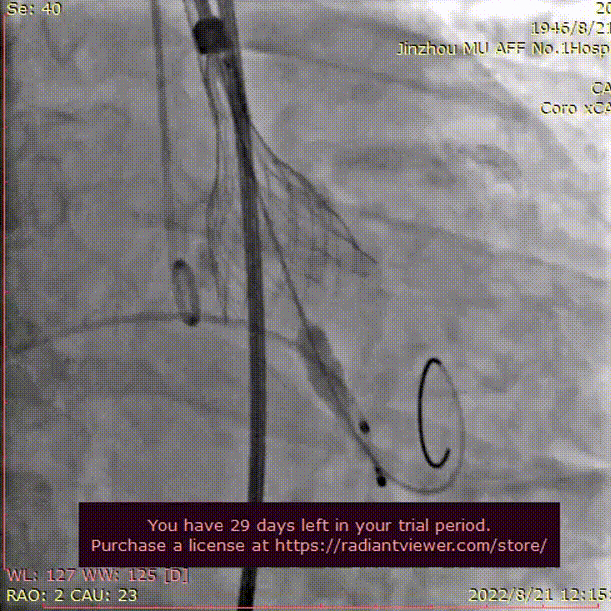

术中影像

LCA术前

LCA术后

RCA术前

RCA术后